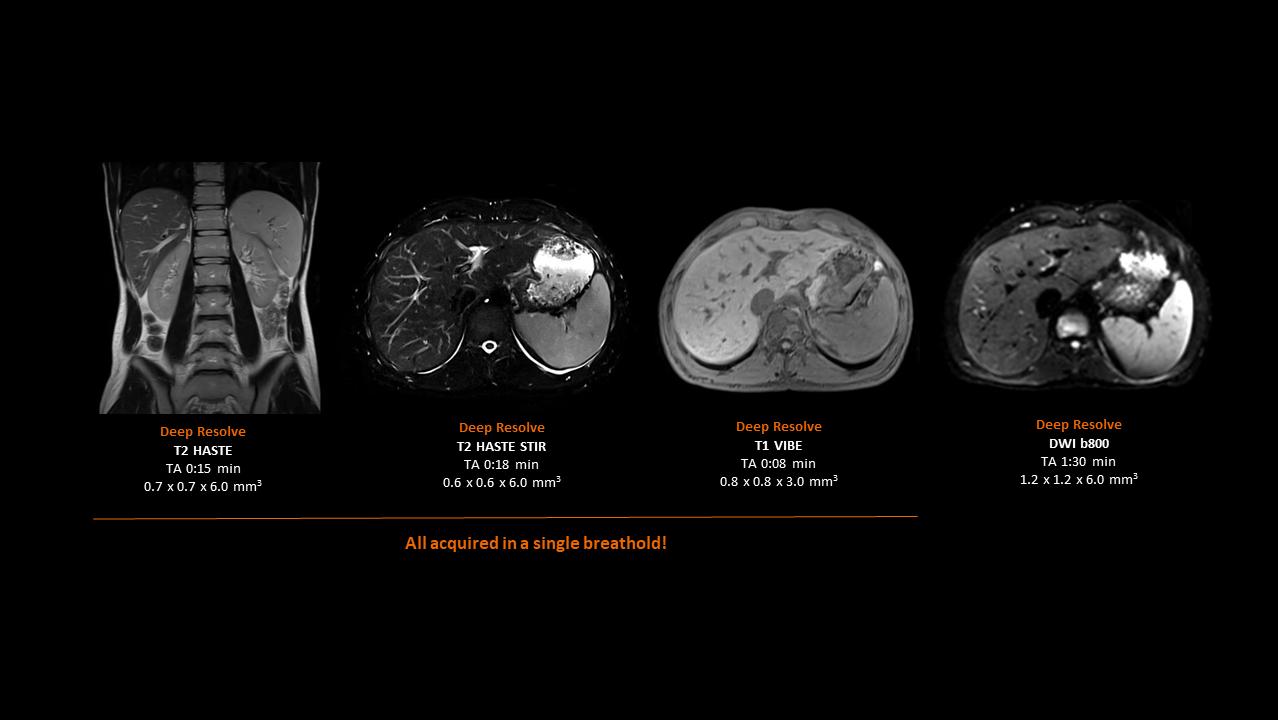

Deep Resolve will be at the forefront of the revolution in MRI acceleration. Deep Resolve will enable our fastest MRI, with images that will have extraordinary clarity, higher clinical productivity, and an even better patient experience. This transformational effect of Deep Resolve is now planned to expand to 3D5, unlocking a new dimension in MRI image resolution and speed.